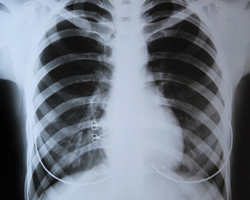

107939Согласно последним наблюдениям ученых из Научно-исследовательского института Сабана при Детской больнице Лос-Анджелеса (The Saban Research Institute of Children’s Hospital Los Angeles) лечение ресвератролом может замедлить дегенеративные изменения, происходящие в легких во время старения. В своей работе исследователи задействовали модель мыши.

Старение легких сопровождается увеличением легочного пространства и снижением функций легких. В свою очередь, это существенные факторы риска, провоцирующие развитие хронических легочных заболеваний. Ученые считают, что их исследование демонстрирует положительное влияние ресвератрола при решении проблем старения легких. С результатами работы можно ознакомиться в журнале «Thorax».

В итоге было установлено, что профилактическое ингаляционное лечение ресвератролом способно замедлить снижение функций легких, увеличение легочного пространства, а также повреждение альвеолярных клеток 2-го типа.

Таким образом, ученые пришли к выводу, что профилактическое лечение ресвератролом может помочь в замедлении старения легких.